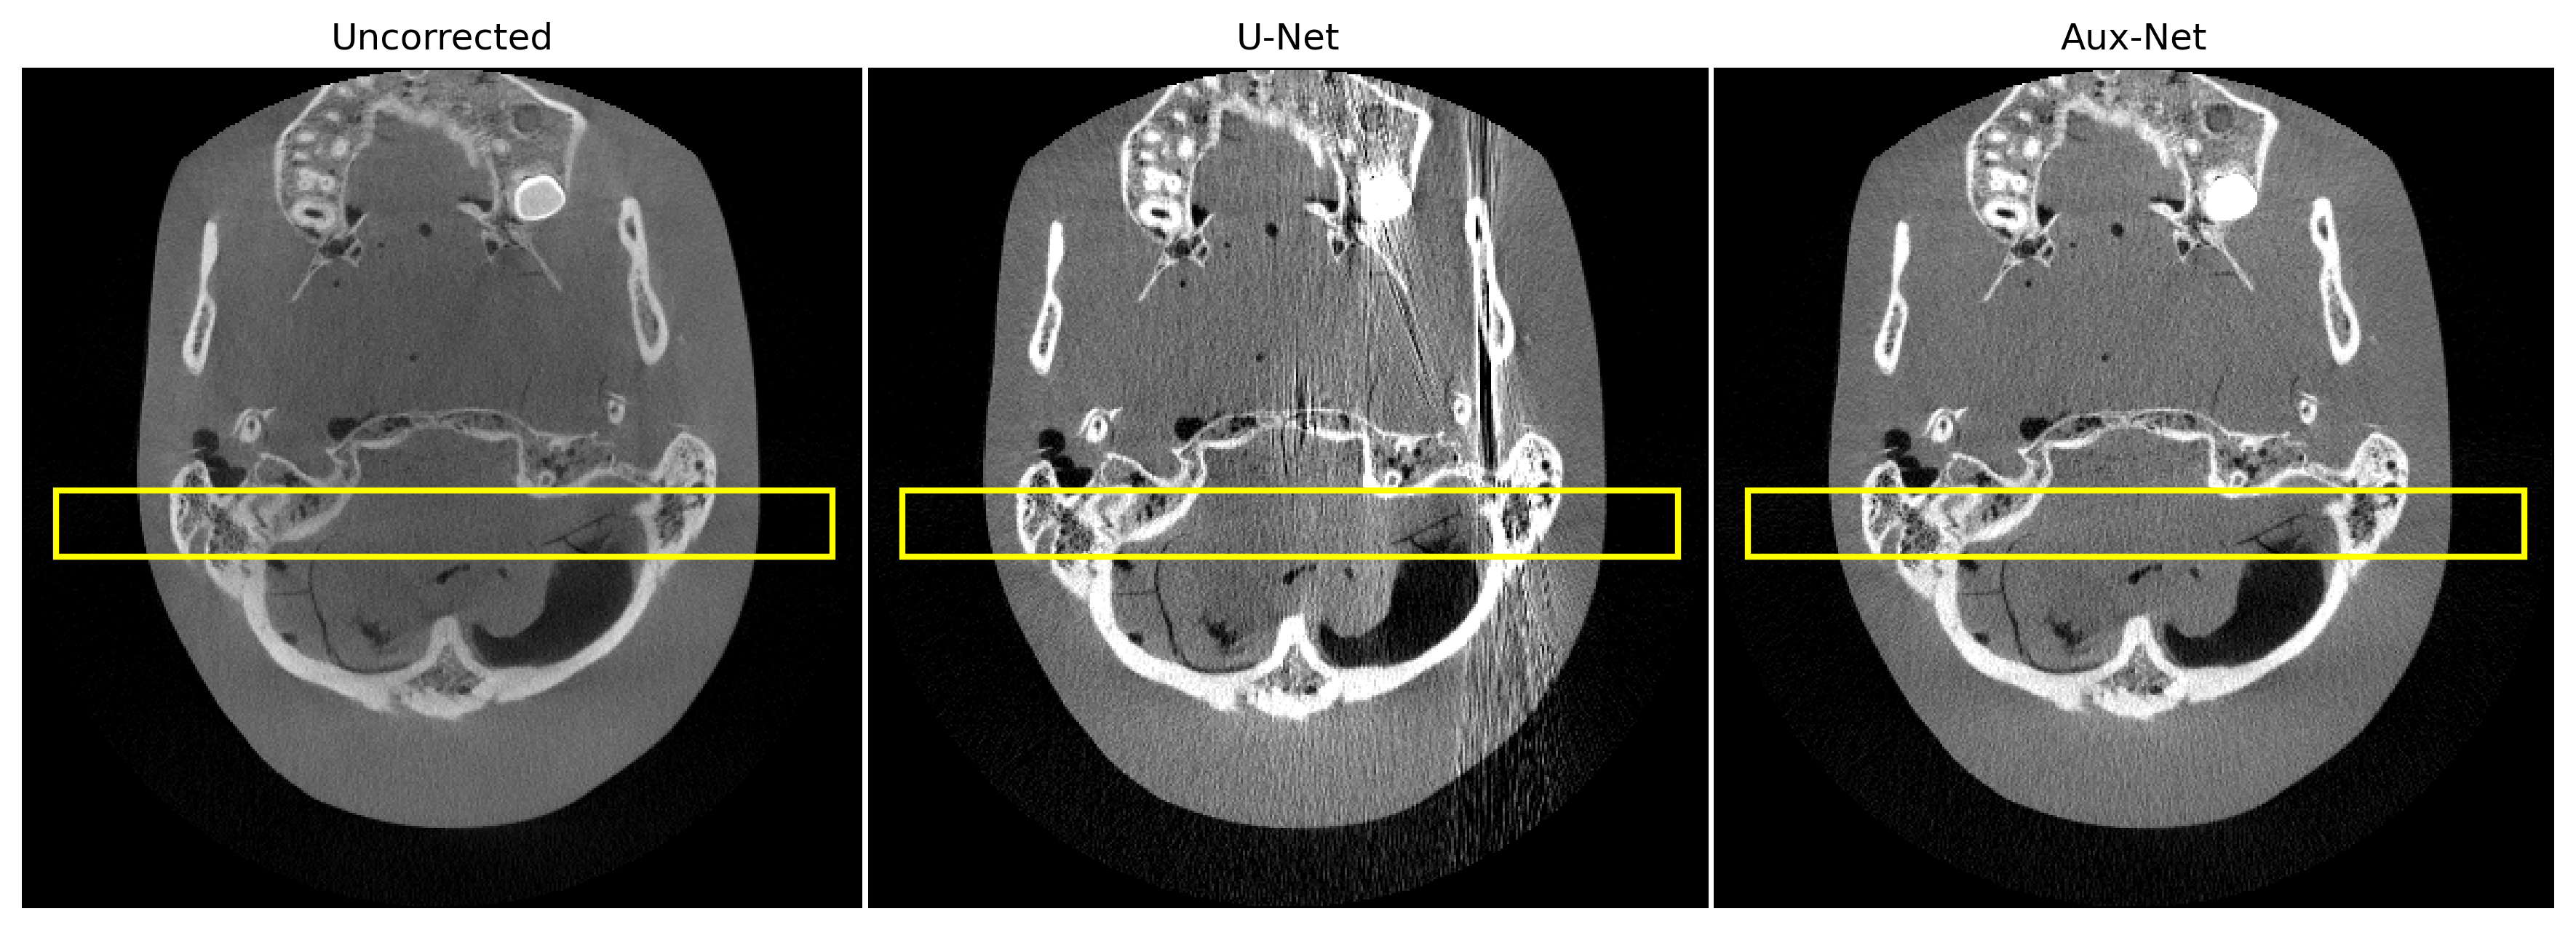

3.2 Scatter estimation on phantom scan

Figure 3 depicts the result of U-Net and Aux-Net based scatter corrected reconstructions for the two axial slices at different locations. The predicted scatter estimates were subtracted from the measurements and reconstruction was done using FDK algorithm for CBCT. The intensity profile is more stable for Aux-Net corrected image slices. Furthermore, the Aux-Net corrected reconstruction is more robust in the presence of high density object in comparison to the U-Net corrected reconstruction.